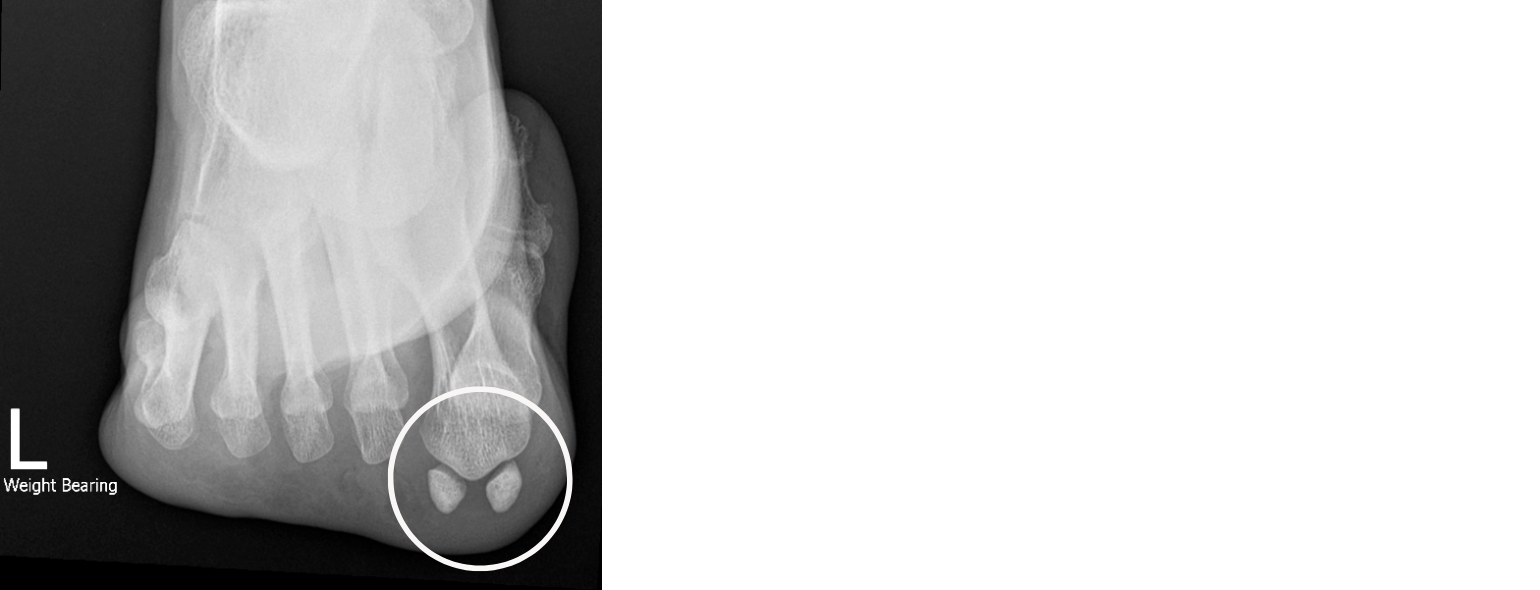

Pain under the big toe joint? It might be your Sesamoids. — Foot & Ankle Pain Under The Big Toe Pad Learn about the causes, symptoms and treatment options, such. big toe pain can result from injury or minor medical conditions, such as arthritis, gout, or sesamoiditis. Learn how to diagnose and treat sesamoiditis, and when to use a sesamoiditis walking boot. sesamoiditis is a condition that causes pain in the ball of the foot, at the base of. Pain Under The Big Toe Pad.

WHAT IS THAT PAIN UNDER MY BIG TOE? (SESAMOIDITIS) Pogo Physio Pain Under The Big Toe Pad It can cause dull pain, swelling and bruising in the ball of the foot. It can be caused by injury, overuse, stress fracture or other conditions. Learn how to diagnose and treat sesamoiditis with footwear, rest, medication and surgery. Learn about the causes, symptoms and treatment options, such. big toe pain can result from injury or minor medical conditions,. Pain Under The Big Toe Pad.